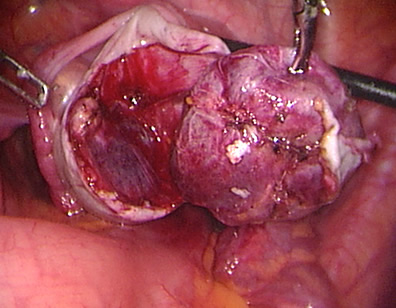

This young lady has an ovarian tumour. See the enlarged left ovary.

The left ovary is opened and the tumour is dissected without compromising the blood supply of the ovary.

The tumour is nearly free and will be extracted with no spillage from the pelvis and for histological analysis.

The ovary is sutured and reconstructed. You may suture using key-hole surgery and with the advantage of visual magnification.

This photo shows the final result. This young patient was able to keep her 2 ovaries. She was discharged home 12 hours later.